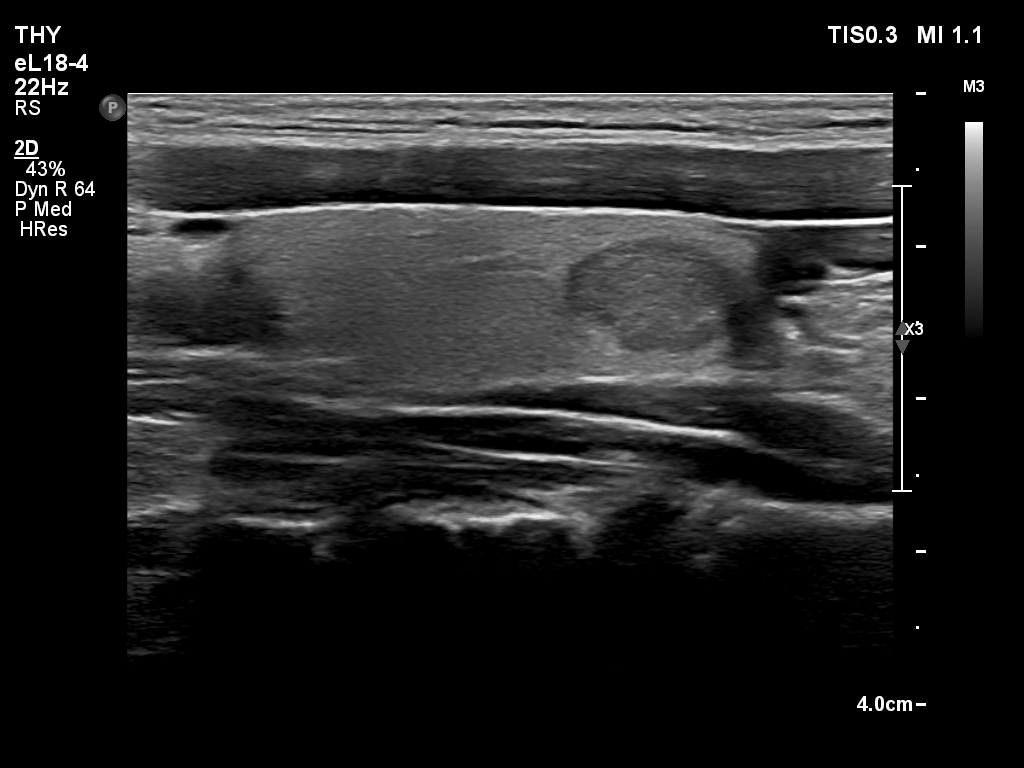

Ultrasonography. The thyroid was echonormal. There was a cystic nodule in the right lobe. The lesion had spongiform portions. The nodules presented all three possible signs of an extrathyroidal extension. There was a minimally hypoechoic nodule in the left lobe.

Cytology of the nodule in the left lobe resulted in benign follicular proliferation.

- The small nodule presented irregular shape but this was not of pathological importance. The hard wall of the carotid artery prevented the nodule from spreading sideways.